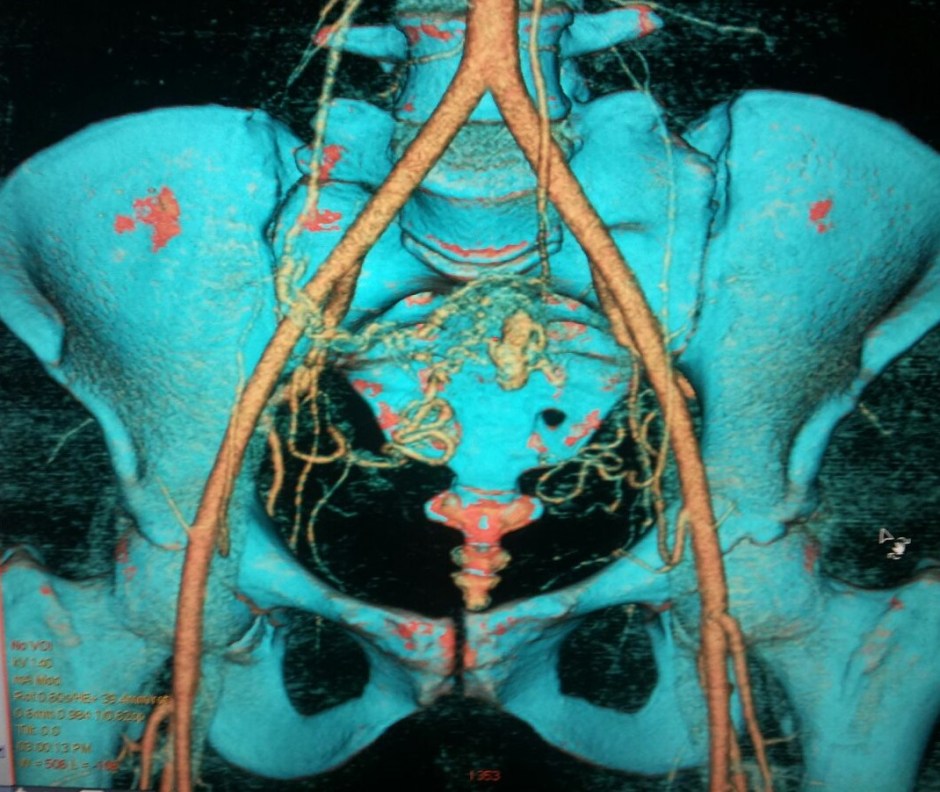

The Contrast Enhanced CT scan pictures are given below.

This was reported as Arterio Venous Malformation, with arterial supply from both the uterine arteries and the venous drainage into the right ovarian vein.

She has been advised embolization treatment of both uterine arteries.